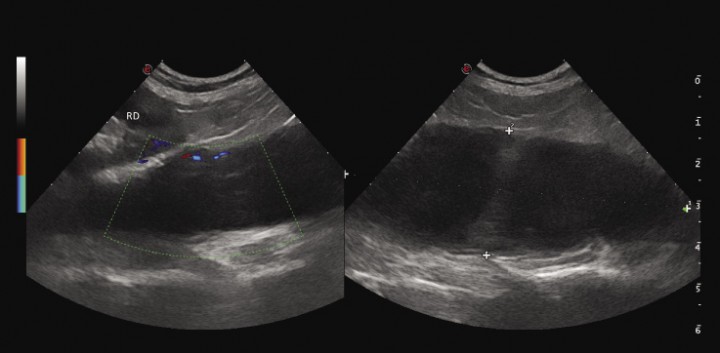

En la exploración ecográfica (Fig. 3) se observó una estructura de contenido hipo-anecoico (sin un claro refuerzo posterior) con cápsula bien definida, asociada a la porción derecha del paquete muscular sublumbar, que se extendía cranealmente hasta la cúpula diafragmática, no pudiendo observar claramente su límite (tamaño difícil de evaluar en corte longitudinal, excede de los 8 cm) y sin cuerpos extraños apreciables. No se apreció neovascularización significativa asociada a la lesión. Se corroboró la posición relativa desplazada de los riñones, por lo demás normales ecográficamente, sin líquido perirrenal apreciable. La grasa retroperitoneal estaba ligeramente hiperecogénica sin atenuación significativa del haz de ultrasonidos. El bazo presentaba ecotextura homogénea e hiperecogénica, sin alteración de la arquitectura parenquimatosa, con cápsula bien definida y regular. Tampoco se hallaron linfadenopatías, reactividad peritoneal ni líquido libre asociado. La exploración ecográfica confirma, por tanto, la sospecha de absceso asociado a la musculatura axial, declinándose el aspirado ecoguiado del líquido debido al peligro de rotura hacia cavidad peritoneal del probable absceso.

<p>Corte sagital en ecografía mediante un abordaje lateral derecho del dorso del abdomen, donde se observa una gran cantidad de líquido encapsulado, con algo de celularidad en suspensión, yuxtapuesto a las vértebras lumbares y dorsal al riñón derecho (RD), que no muestra alteraciones por su parte. En la exploración Doppler sólo se observa neovascularización en la cápsula de la lesión.</p>

Corte sagital en ecografía mediante un abordaje lateral derecho del dorso del abdomen, donde se observa una gran cantidad de líquido encapsulado, con algo de celularidad en suspensión, yuxtapuesto a las vértebras lumbares y dorsal al riñón derecho (RD), que no muestra alteraciones por su parte. En la exploración Doppler sólo se observa neovascularización en la cápsula de la lesión.